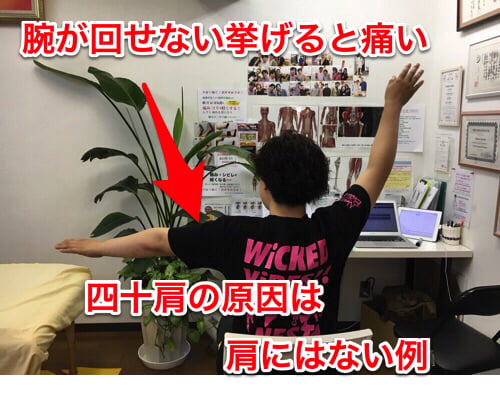

先日ご来院頂いた四十肩と指の痛みでお困りのお客様。

実際に腕を動かして頂くと

左腕をここまで上げると肩の付け根付近 の脇あたりに痛みが出てしまいます。

横から腕を上げる際もこんな感じで痛みがでて上がらない。

四十肩は多くの場合、肩そのもの、関節や骨に異常はありません。

でも通常、どこの院に行っても肩しか診てもらえません。

四十肩を引き起こし大きな原因の1つは手首のねじれ。

今回の四十肩の原因は手首と肘のネジレが根本原因でした。